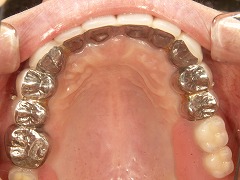

Case.1 コーヌスクローネ義歯症例(装着後25年経過)

年齢層 | 70代 男性 |

どんなお悩み | 他院で入れ歯を作られたが、入れ歯が痛くてかめない。話をする際に話しずらい、発音しずらいというお悩みがありました。治療内容 かぶせ物を外して、残ってる歯に二重に冠をかぶせて入れ歯をとめる義歯を制作(コーヌスデンチャー) |

治療 期間 | 治療期間は3か月程度 |